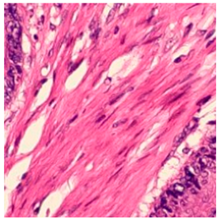

Related Work

2.4. Model Interpretability

3.6. Visualizing Interpretability in CRC Classification Using ADFMs

4. Discussion